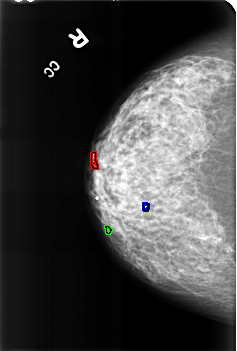

B_3178_1.RIGHT_CC

FILE: B_3178_1.RIGHT_CC.OVERLAY

TOTAL_ABNORMALITIES 3

ABNORMALITY 1

LESION_TYPE OTHER

ASSESSMENT 2

SUBTLETY 4

PATHOLOGY BENIGN_WITHOUT_CALLBACK

TOTAL_OUTLINES 1

BOUNDARY

ABNORMALITY 2

LESION_TYPE CALCIFICATION TYPE LUCENT_CENTER DISTRIBUTION N/A

SUBTLETY 5

ABNORMALITY 3